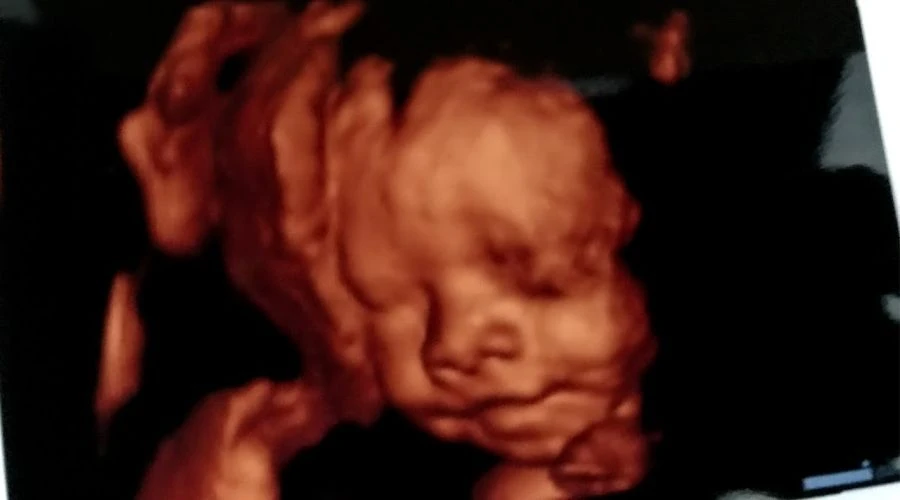

El 3 de octubre, en el marco de la marcha A favor de la mujer y de la vida, que congregó a 300 mil personas en Ciudad de México y alrededor de un millón en todo el país, un médico realizó una ecografía a Ana, una adolescente de 15 años con 38 semanas de embarazo.

El conmovedor momento en que realizan una ecografía en la marcha @Afavormujervida #MexicoEsProvida #MeLateElCorazón https://t.co/1IfdgukGrT pic.twitter.com/z2mga0PgOp

— David Ramos (@YoDash) October 3, 2021¡Así suena el corazón en el vientre materno! @Afavormujervida #MexicoEsProvida #MeLateElCorazón https://t.co/1IfdgukGrT pic.twitter.com/9sGkpXrZge

— David Ramos (@YoDash) October 3, 2021El video de la ecografía motivó la ira de los promotores del aborto, que realizaron múltiples insultos y amenazas.

Al mismo tiempo, el video del ultrasonido se viralizó, llegando a cerca de 11 millones de personas, con alrededor de 2 millones de reproducciones.